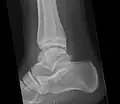

Ankle

Accessory bones at the ankle mainly include:

- Os subtibiale, with a prevalence of approximately 1%.[14] It is a secondary ossification center of the distal tibia that appears during the first year of life, and which in most people fuses with the shaft at approximately 15 years in females and approximately 17 years in males.[14]

- Os subfibulare, with a prevalence of approximately 0.2%.[15]

Os trigonum (further described below) may also be seen on an ankle X-ray.